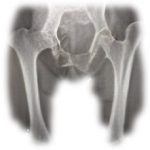

CADERA

Lesiones de la cadera

Las lesiones de la cadera son bastante comunes. Su articulación está formada por la cabeza del fémur y el acetábulo (porción articular cóncava de la superficie de la pelvis). Está diseñada para soportar el peso del cuerpo, rodeada por grupos musculares muy potentes y presenta una gran estabilidad (se trata de una bola situada dentro de una copa).